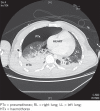

Surgical repair of pulmonary vein injury from blunt trauma

Pulmonary vein deceleration injury is rare and patients can be deceptively stable for a period after injury. Quick diagnosis and transfer to the operating theatre is the only way to treat this potentially lethal injury successfully. Techniques of repair are a useful addition to the cardiovascular surgeon's repertoire.